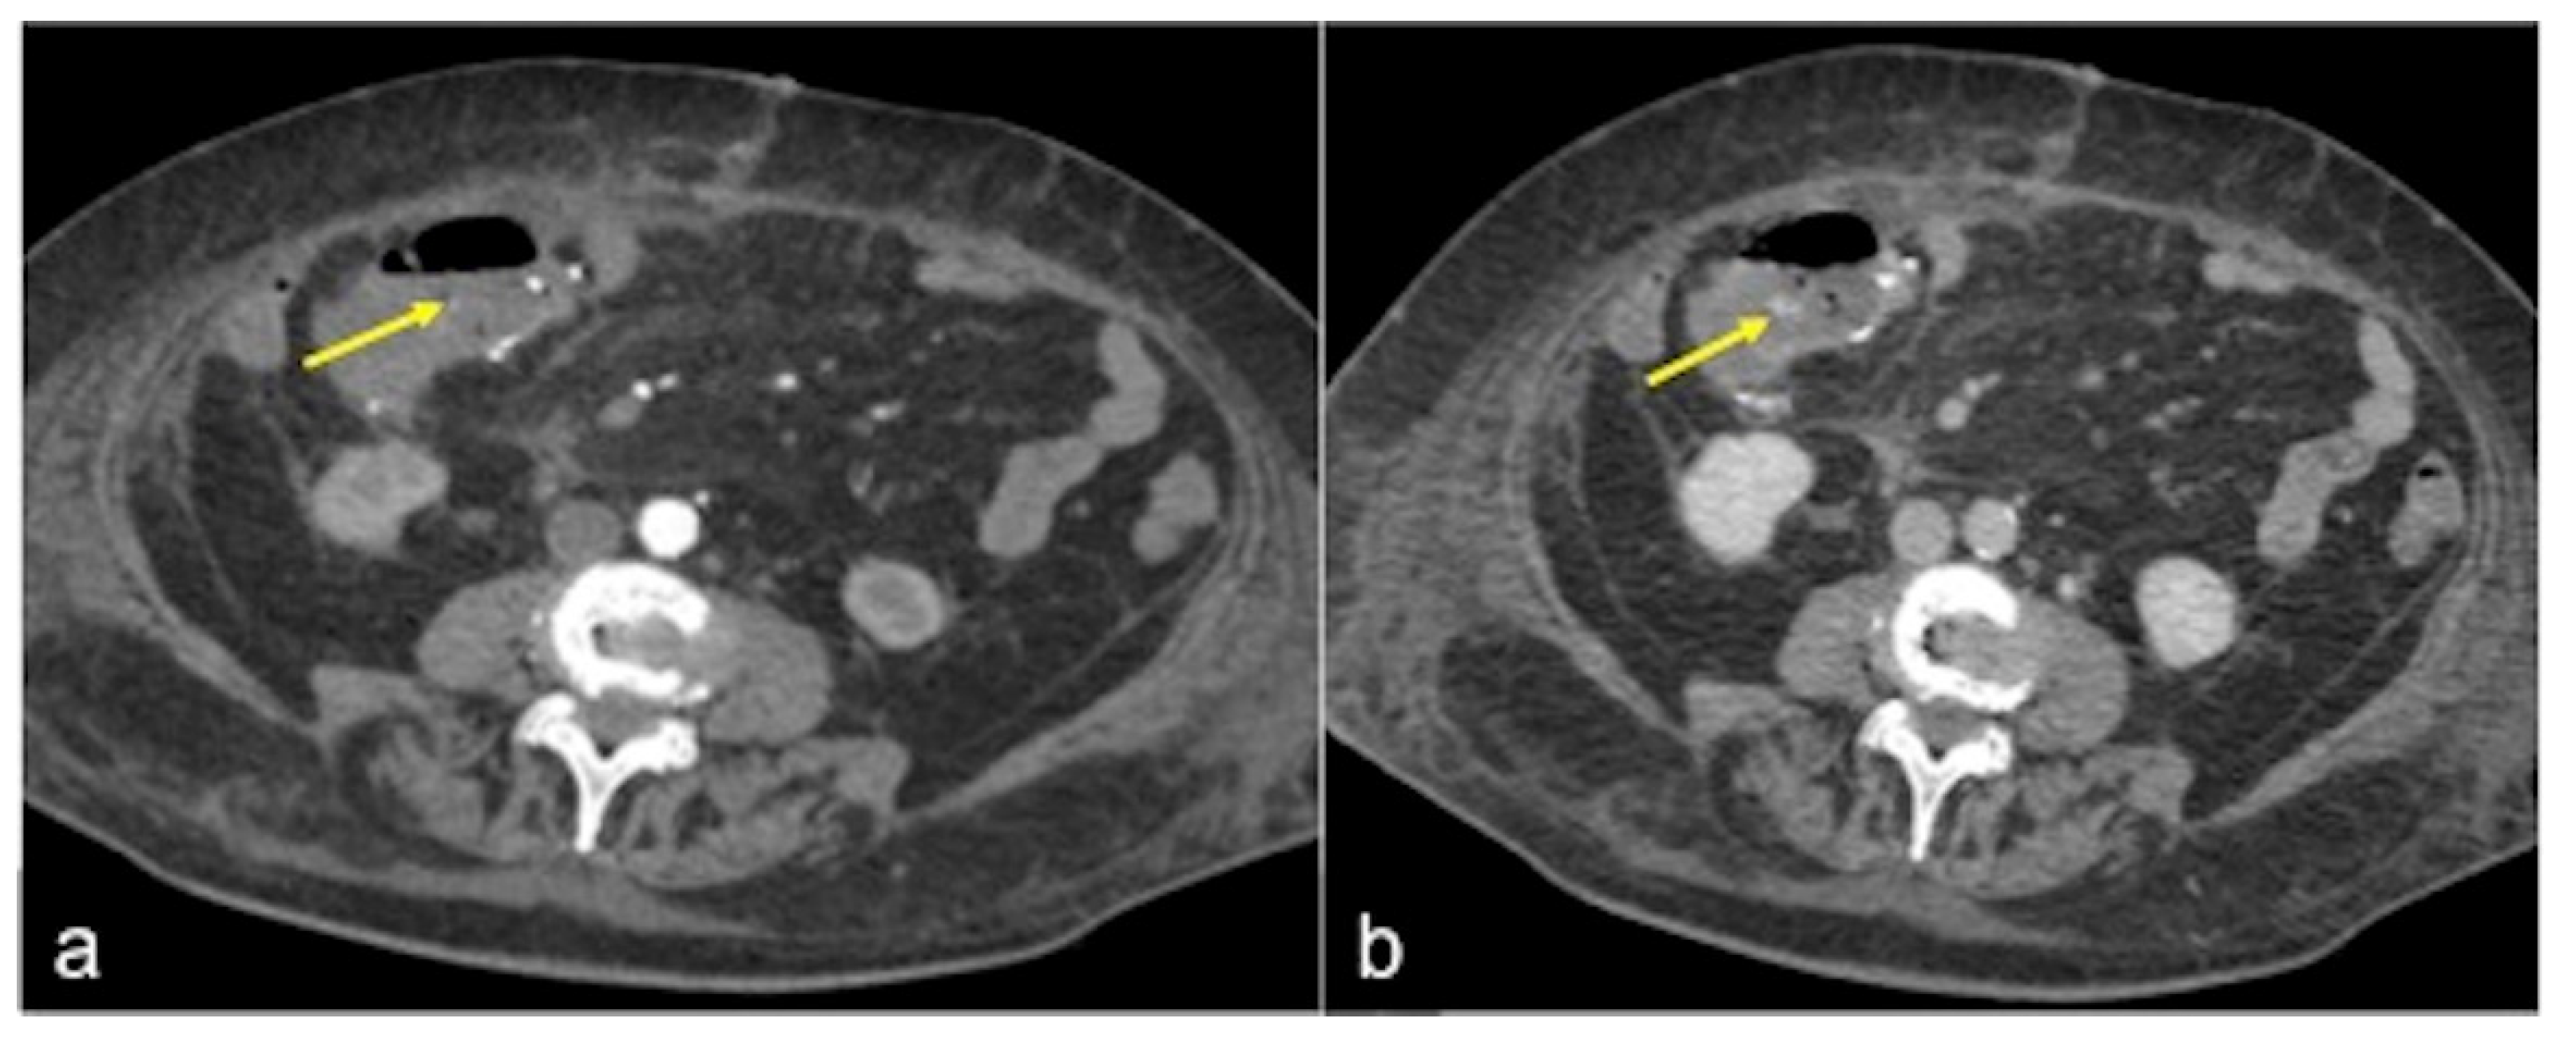

| Tumour (Figure 29) | Asymptomatic or bleeding. | Irregular wall thickening with foci of active bleeding. |